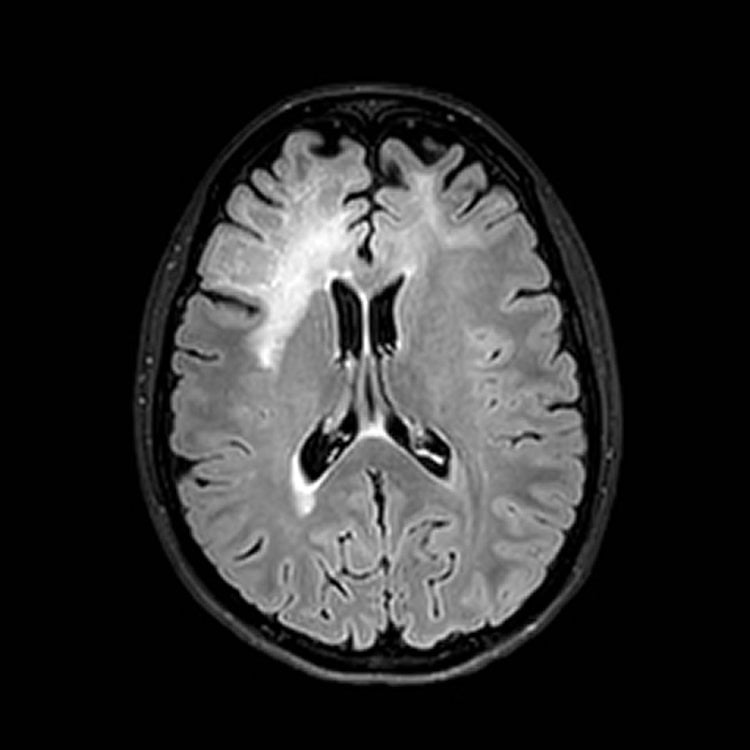

Humans carry a multitude of viruses and bacteria in their gut, on their skin and in other organs. Often, these are involved in important bodily functions. Under certain conditions, however, some can also cause diseases. The JC virus, a member of the polyoma tumor virus family, is a prime example. This pathogen was first isolated from the brain of a patient who was suffering from a rare brain disease known as progressive multifocal leukoencephalopathy (PML). The virus, which more than 60 percent of the global population are infected with, normally resides in the kidneys and certain other organs. JC virus can trigger the PML infection in the brain, which, in most cases, is fatal.

Two studies conducted by an international team of researchers from the University of Zurich, the University Hospital Zurich, the National Institutes of Health in the USA, San Raffaele Hospital in Milan, the University of Tübingen, and the UZH spin-off Neurimmune now reveal that the antibodies in PML patients often fail to recognize the JC virus they are infected with. “In healthy people, the disease never breaks out as the immune system keeps it well under control. Once the immune system is compromised, however, such as in patients with tumors, leukemia, AIDS, autoimmune diseases and certain immunosuppressive treatments, the JC virus is able to alter its genetic information and infect the brain,” explains Roland Martin, professor of neurology at the University of Zurich.

Image Credit: The images are credited to Neuroradiology, USZ